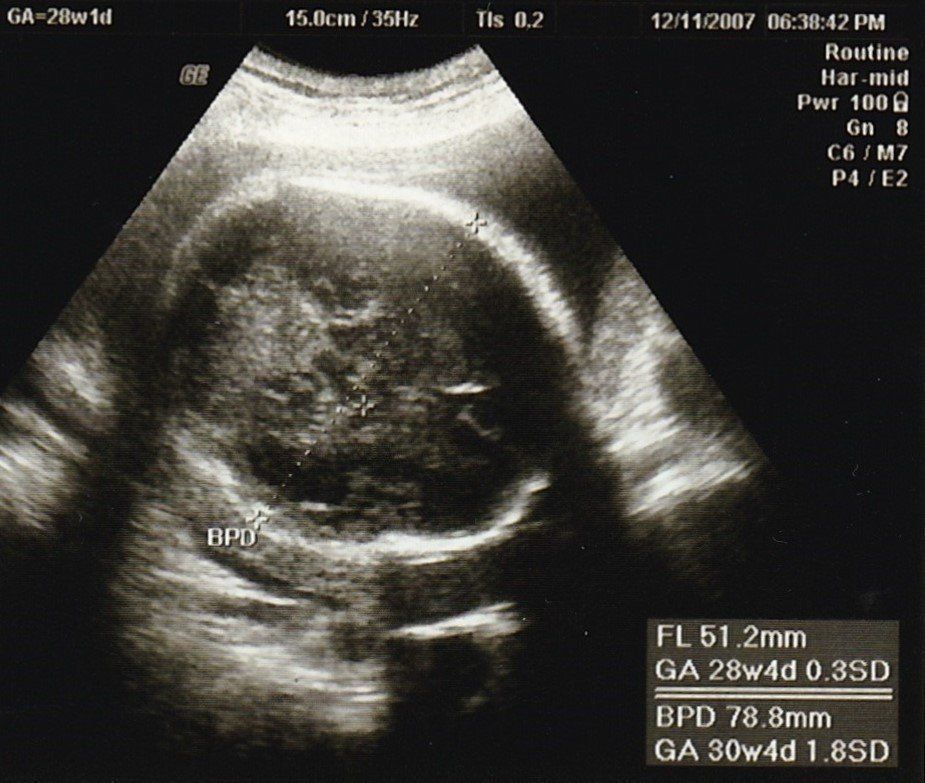

妊娠28週目のエコー写真

この辺から、少し動くだけで息切れするようになり、寝ても起きても息苦しさを感じていました。思ったより体力がなくなり、マタニティーヨガに通ったり、胎教にとクラシックや童謡や英語の曲などを聴いたりして気分転換を心がけて過ごしました。